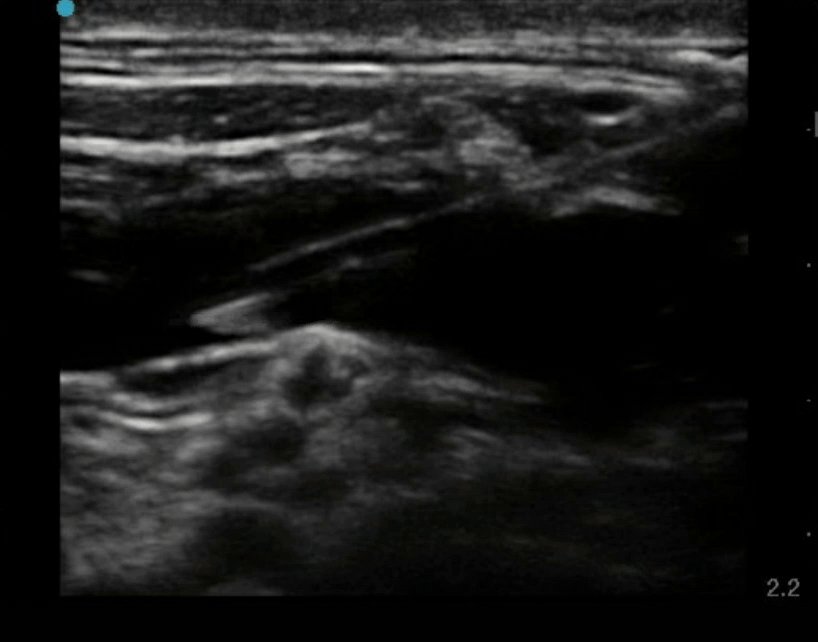

In this case, a nerve bundle is seen! This reminds us of the importance of identifying and avoiding neighboring key structures, such as nerves. Nerve injury has been reported following central venous cannulation.

Vessel Access (continued)

When the nerve was noticed to be in a precarious position, the needle was repositioned to avoid accidental nerve injury. Imagine trying to avoid this nerve without ultrasound!